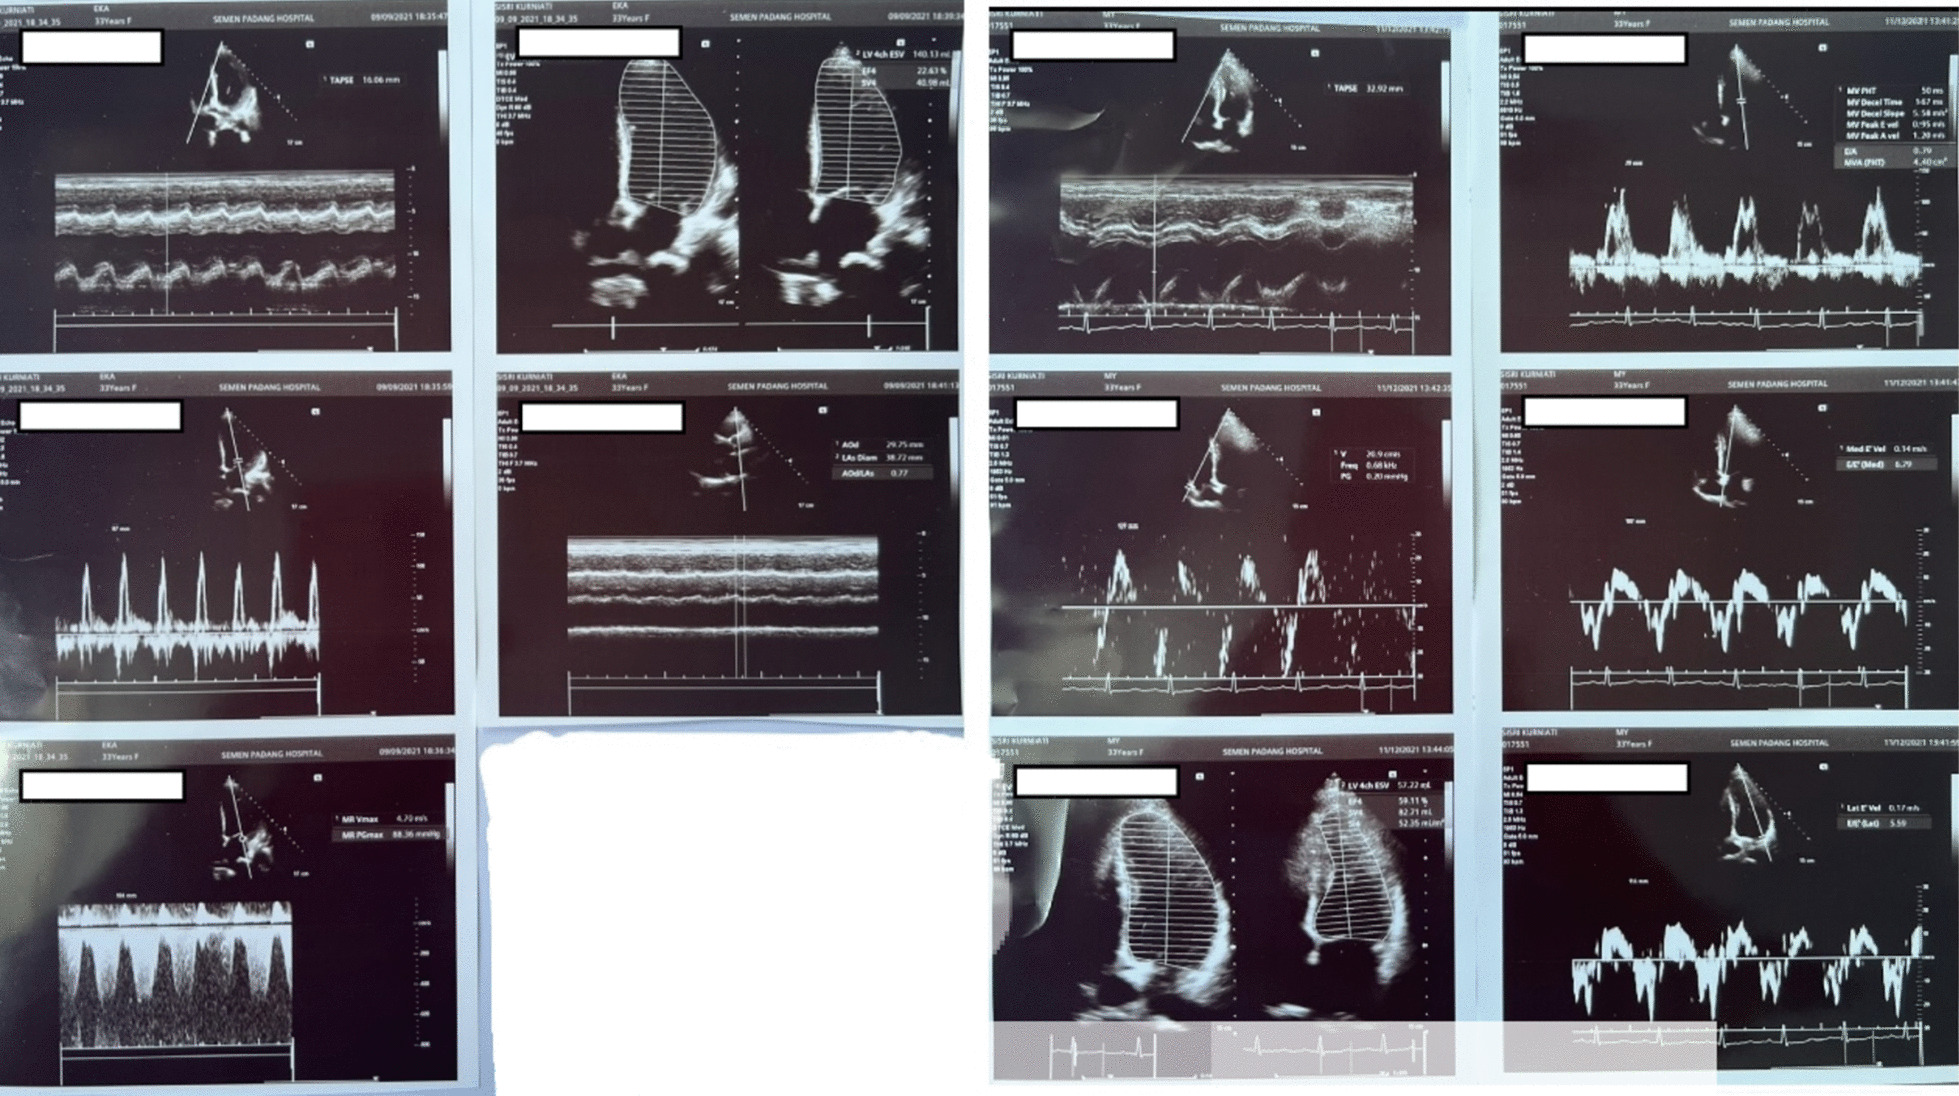

A 33-year-old Asian woman, in her third aterm pregnancy, ASA 2 with severe preeclampsia, was admitted to the ICU after caesarian section and tubectomy surgery due to shortness of breath and chest discomfort. The patient has a past medical history of severe preeclampsia in two previous pregnancies but no history of PPCM nor history of PPCM in her family, the patient also denied any history of congenital heart disease and history of heart failure. Her vital signs on ICU arrival were: blood pressure 136/92 mmHg, heart rate 150 beats/min, respiratory rate 38–40 breaths/min, temperature 38 ºC, saturation 95% with simple mask oxygen flow 6 L/min. She was awake and alert and was in a diaphoretic and tachypneic state. Lung examination revealed wet crackles throughout both lung fields. Her abdomen was diffusely tender. She had pretibial pitting edema. The neurologic examination yielded no abnormalities. Laboratory investigations at admission revealed white blood cell count was 20.300/mm3, hemoglobin and hematocrit were 13.6 g/dL, and 41% subsequently. Arterial blood gas analysis values on oxygen 6 L/min results were: pH 7.43; PaCO2 27 mmHg; PaO2 122 mmHg; PaO2/FiO2 ratio of 244; HC 17.7 mmol; BE − 3 mmol/L; SaO2 98%. PT and aPTT were within normal limits, but the D Dimer value was increasing by 1999 ng/mL. Serum Na+ was 137 mmol/L; K+ 3.5 mmol/L; calcium total 9.9 mg/dL; ureum 25 mg/dL; creatinine 0.4 mg/dL; SGOT and SGPT within normal limits but her bilirubin values were increased (total 3 mg/dL; direct 2.5 mg/dL, indirect 0.5 mg/dL) and lactate 3.3 mmol/L. The electrocardiogram (ECG) showed sinus tachycardia with nonspecific ST-T wave changes. The chest X-ray examination showed cardiomegaly with increased interstitial markings (Fig. 1). Echocardiography revealed all chamber dilation with marked global hypokinesis, decreased systolic function of left and right ventricles, mild–moderate mitral regurgitation, with an ejection fraction of 22% (Fig. 2).

Fig. 2.

Echocardiography examination (left: post-operative day 0, right: 6 months later)

The patient was satisfied with the treatment as her symptoms reduced two weeks after discharge and she had no symptoms 3 months after discharge. Home medications (Ramipril and Bisoprolol) were discontinued after three-months follow up. Six months after discharge, patient showed stable cardiomyopathy and well-controlled hypertension, and a repeat echocardiography at the same point showed an improved ejection fraction from 22 to 60%.